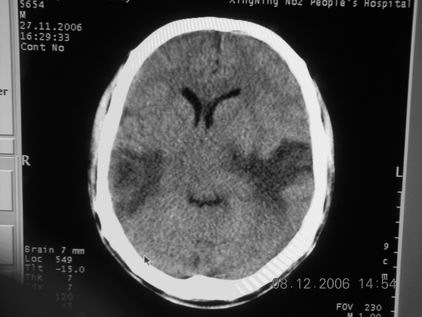

标题: CT11164:男,46岁,白血病患者,,大家看看. [打印本页]

标题: CT11164:男,46岁,白血病患者,,大家看看.

以前的片子,病史忘了,男,46岁,白血病患者,后来到中山二院诊断为

谁见过白血病中枢系统改变是怎么样的吗?

多发性脑脓肿?

白血病脑浸润。

支持白血病脑浸润.

1 多发脑脓肿可能性大.>2 白血病浸润.

白血病脑浸润。没见过!但结合病史应首先考虑此病。

支持白血病脑浸润

结合病史考虑白血病脑浸润。

结合白血病病史,支持考虑白血病脑浸润。

结合病史考虑白血病脑浸润